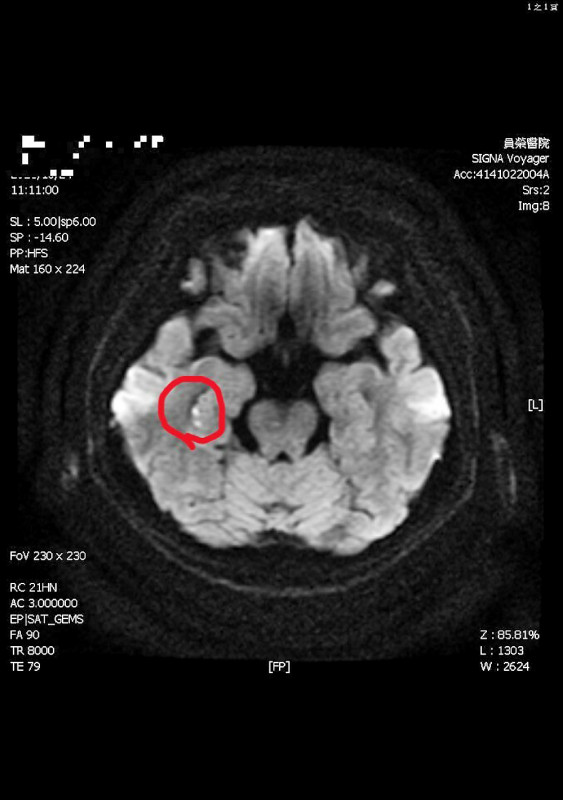

彰化縣員榮醫院神經內科醫師陳彥秀表示,經核磁共振(MRI)檢查顯示,婦人右側海馬迴出現一點亮亮影像,證實是因情緒激動引發局部中風,導致「短暫性全面失憶」。